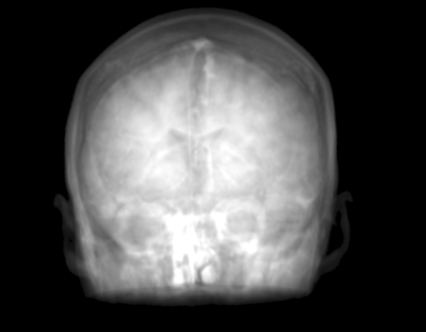

The proposed approach was successful in generating X-ray projections with a contrast similar to the one seen in true fluoroscopic X-ray images. Quantitative results of the generated projection images for all patients are presented in Tab. 2 and for the different network architectures in Tab. 2. In Fig. 2a to 2e the behavior of the MSE and SSIM w.r.t the projection angle is presented. Additional qualitative results of the proposed projection image-to-image translation pipeline for different patient data sets are shown in Fig. 3a to 3c. In Fig. 4 the influence of the modified network architecture, as well as the weighted loss w.r.t. to the edge map are presented.

MRI projection Generated projection Label projection

The improvement in our method compared to the baseline method is demonstrated by a decreased MSE, increased SSIM, and PSNR in Tab. 2. When examining Fig. 4a to 4c, improvements can be observed in the overall increased contrast of high-frequency details. Using the originally proposed architecture [5, 6], which gathers the residual blocks at the lowest resolution level, results in overall blurrier results and missing bone structures as seen in Fig. 4a. In contrast, the projections generated with the edge-weighted loss resemble the label images more closely. This can especially be observed at the base of the head. The projections created without the weighting also produce many high-frequency details in this region, however, these are less specific in comparison with the edge-weighted results. This results in decreased MSE and increased SSIM and PSNR of the projections synthesized using our approach. In addition, unnatural holes in the brain are generated by the baseline architecture. A possible explanation for the fluctuations in the error measure shown in Fig. 2a and 2b is that in our trajectory in the angles around 45 and 135 degrees the projection rays are cast from the side through the brain while around 90 and 180 degrees the angle of incidence is from the front or back side of the skull. In the first case this results in projections that exhibit large homogeneous areas which are easier to synthesize. In the second case, however, the high-frequency edges from the eyes, jawbone, etc. are the dominant structures in the image. A limiting factor of this study is the low number of patient datasets available. However, the amount of variation introduced by forward projecting the volumes is large. Varying projective geometries account for distinctively different structural appearance of the resulting projections. What is of course not covered by these transformations are unique characteristics of individual patients or different pathologies. To investigate the possible translation outcome of these properties larger datasets are required in the future. Also details that are not visible in the MRI projections can not be transferred to the generated images. An example would be interventional devices that are X-ray but not MR sensitive. Regarding subsequent post-processing applications, the question arises how this missing information in the generated projection images should be dealt with, which is subject to future work.